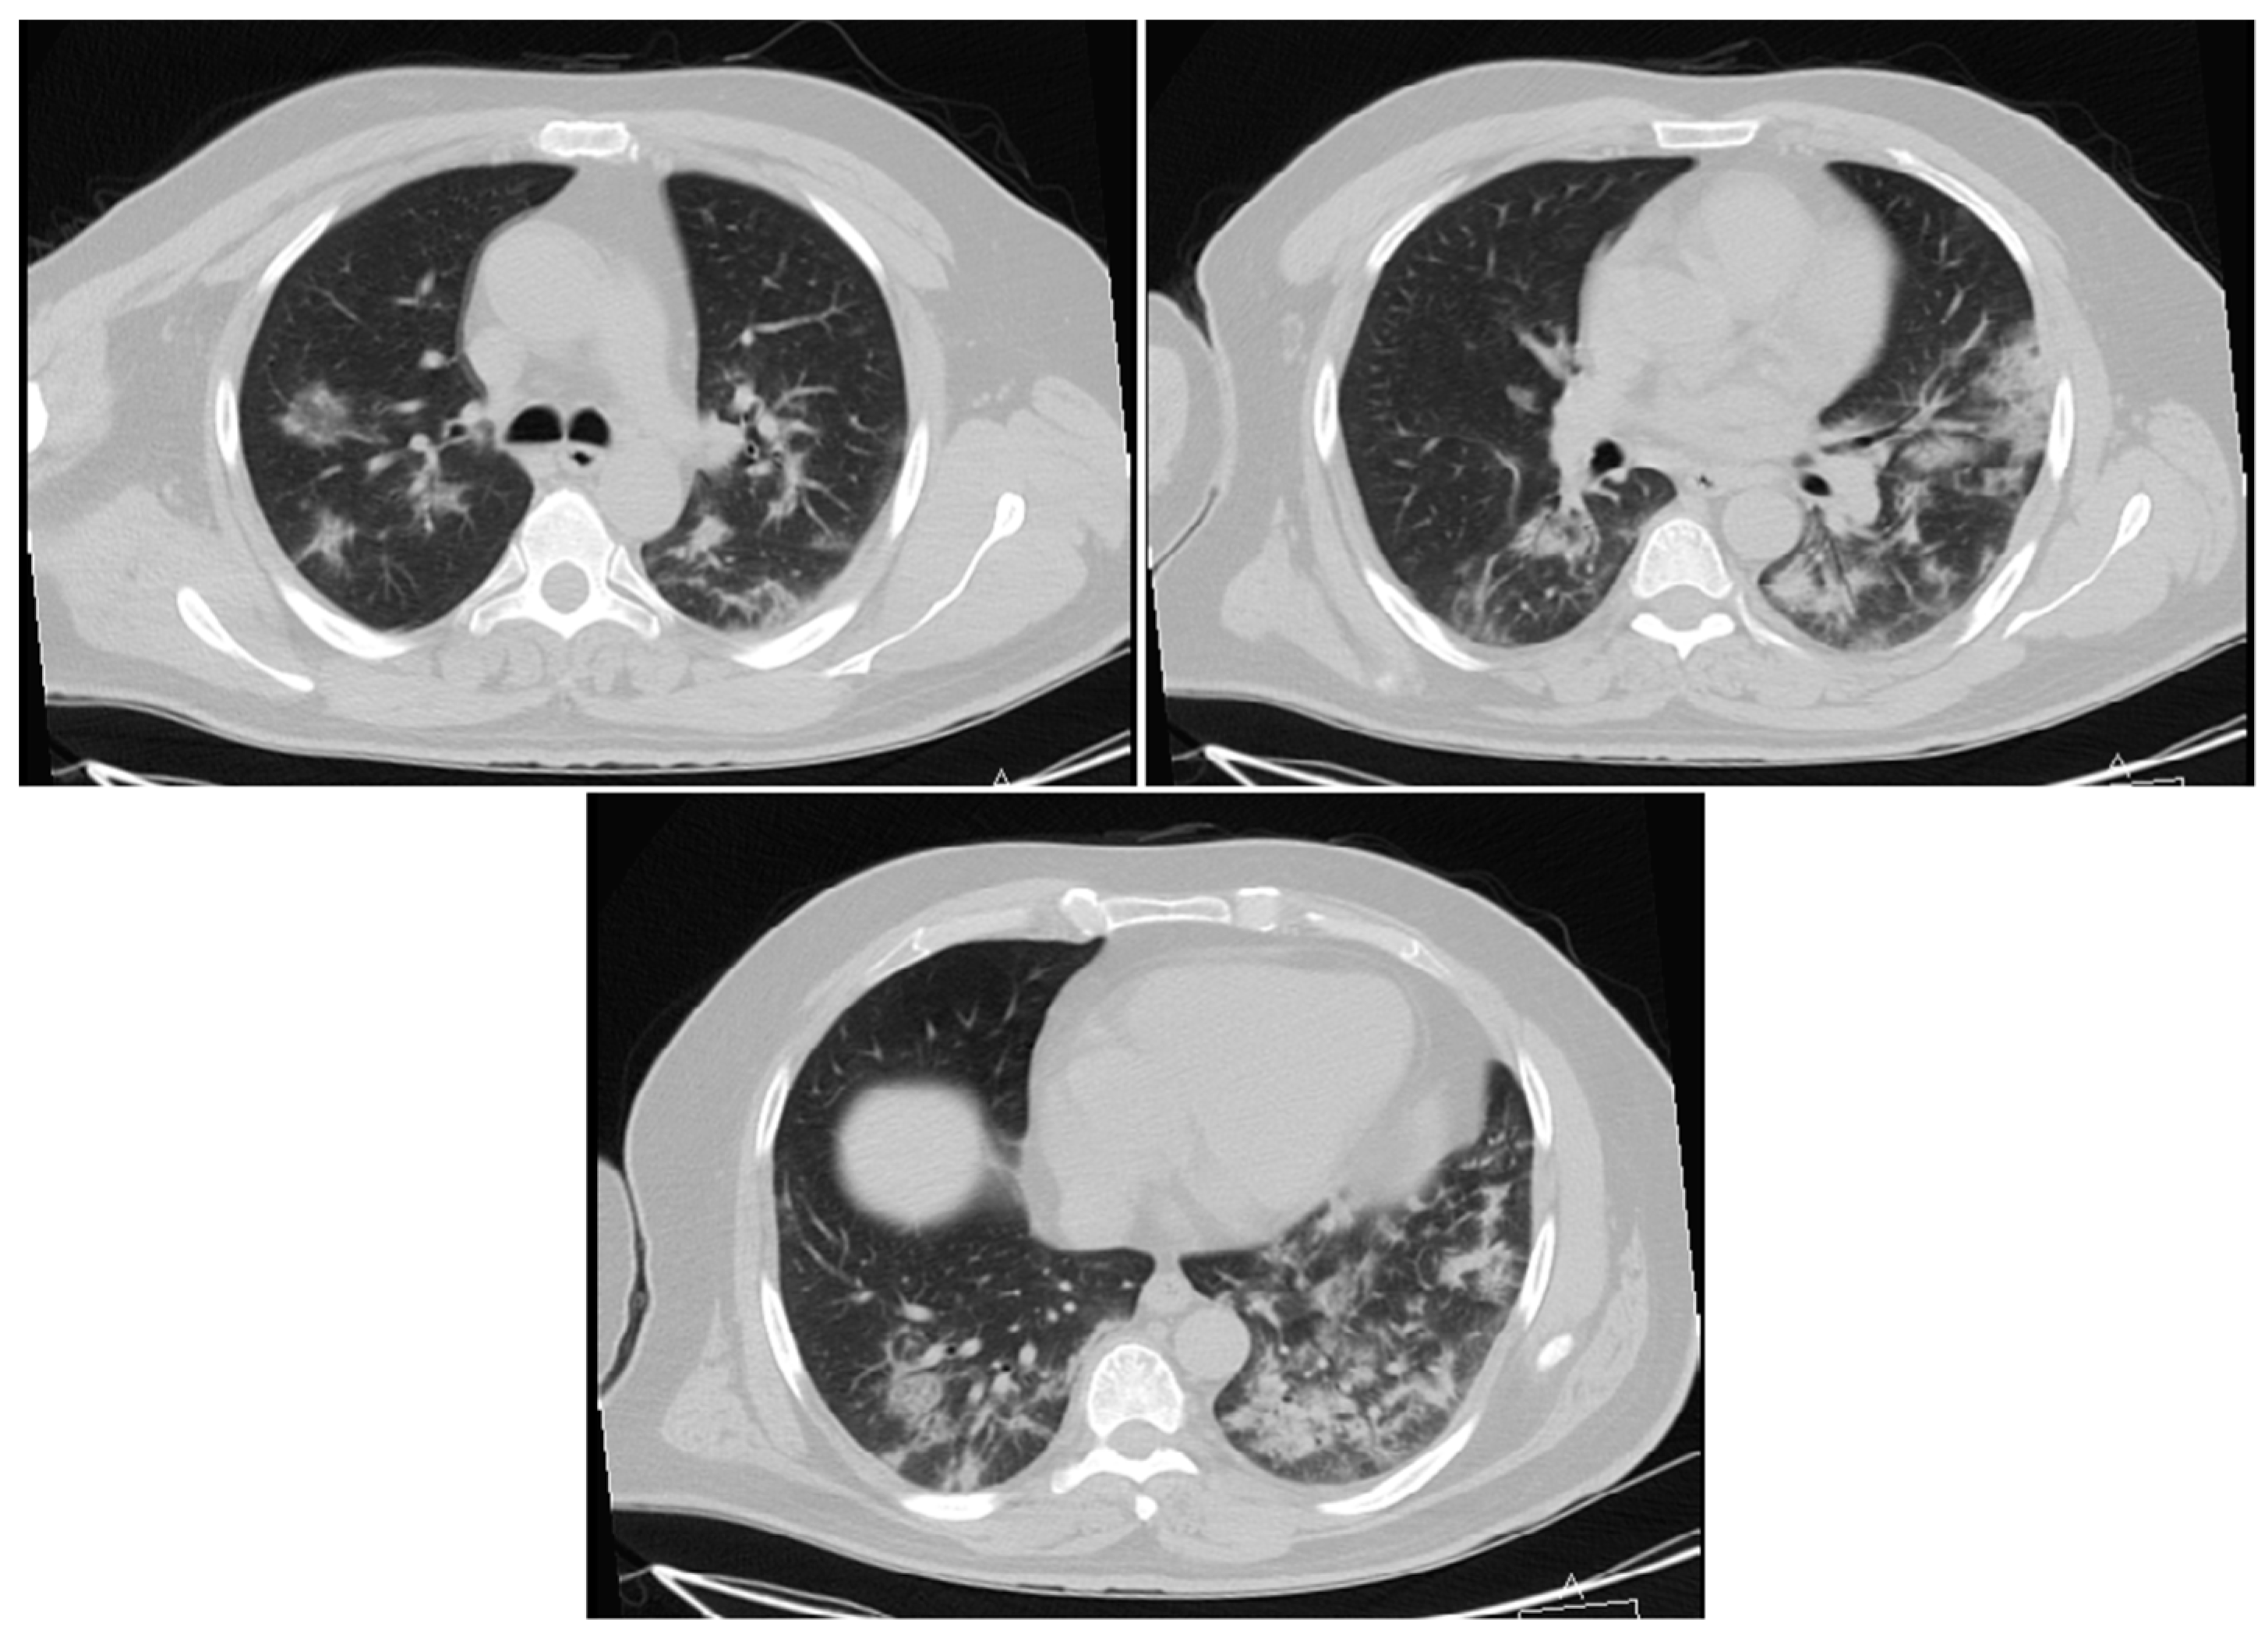

3.1.1. Cases Reports from Iran

Case 1

Case 2

Case 3

Case 4

Case 5

- Mahdavi, A.; Khalili, N.; Davarpanah, A.H.; Faghihi, T.; Mahdavi, A.; Haseli, S.; Sabri, A.; Kahkouee, S.; Kazemi, M.A.; Mehrian, P.; et al. Radiologic Management of COVID-19: Preliminary Experience of the Iranian Society of Radiology COVID-19 Consultant Group (ISRCC). Iran. J. Radiol. 2020. [Google Scholar] [CrossRef]

- Pan, Y.; Guan, H. Imaging changes in patients with 2019-nCov. Eur. Radiol. 2020. [Google Scholar] [CrossRef]

- Ng, M.-Y.; Lee, E.Y.P.; Yang, J.; Yang, F.; Li, X.; Wang, H.; Lui, M.M.-S.; Lo, C.S.-Y.; Leung, B.; Khong, P.-L.; et al. Imaging Profile of the COVID-19 Infection: Radiologic Findings and Literature Review. Radiol. Cardiothorac. Imaging 2020. [Google Scholar] [CrossRef]

- Zu, Z.Y.; Jiang, M.D.; Xu, P.P.; Chen, W.; Ni, Q.Q.; Lu, G.M.; Zhang, L.J. Coronavirus Disease 2019 (COVID-19): A Perspective from China. Radiology 2020. [Google Scholar] [CrossRef]